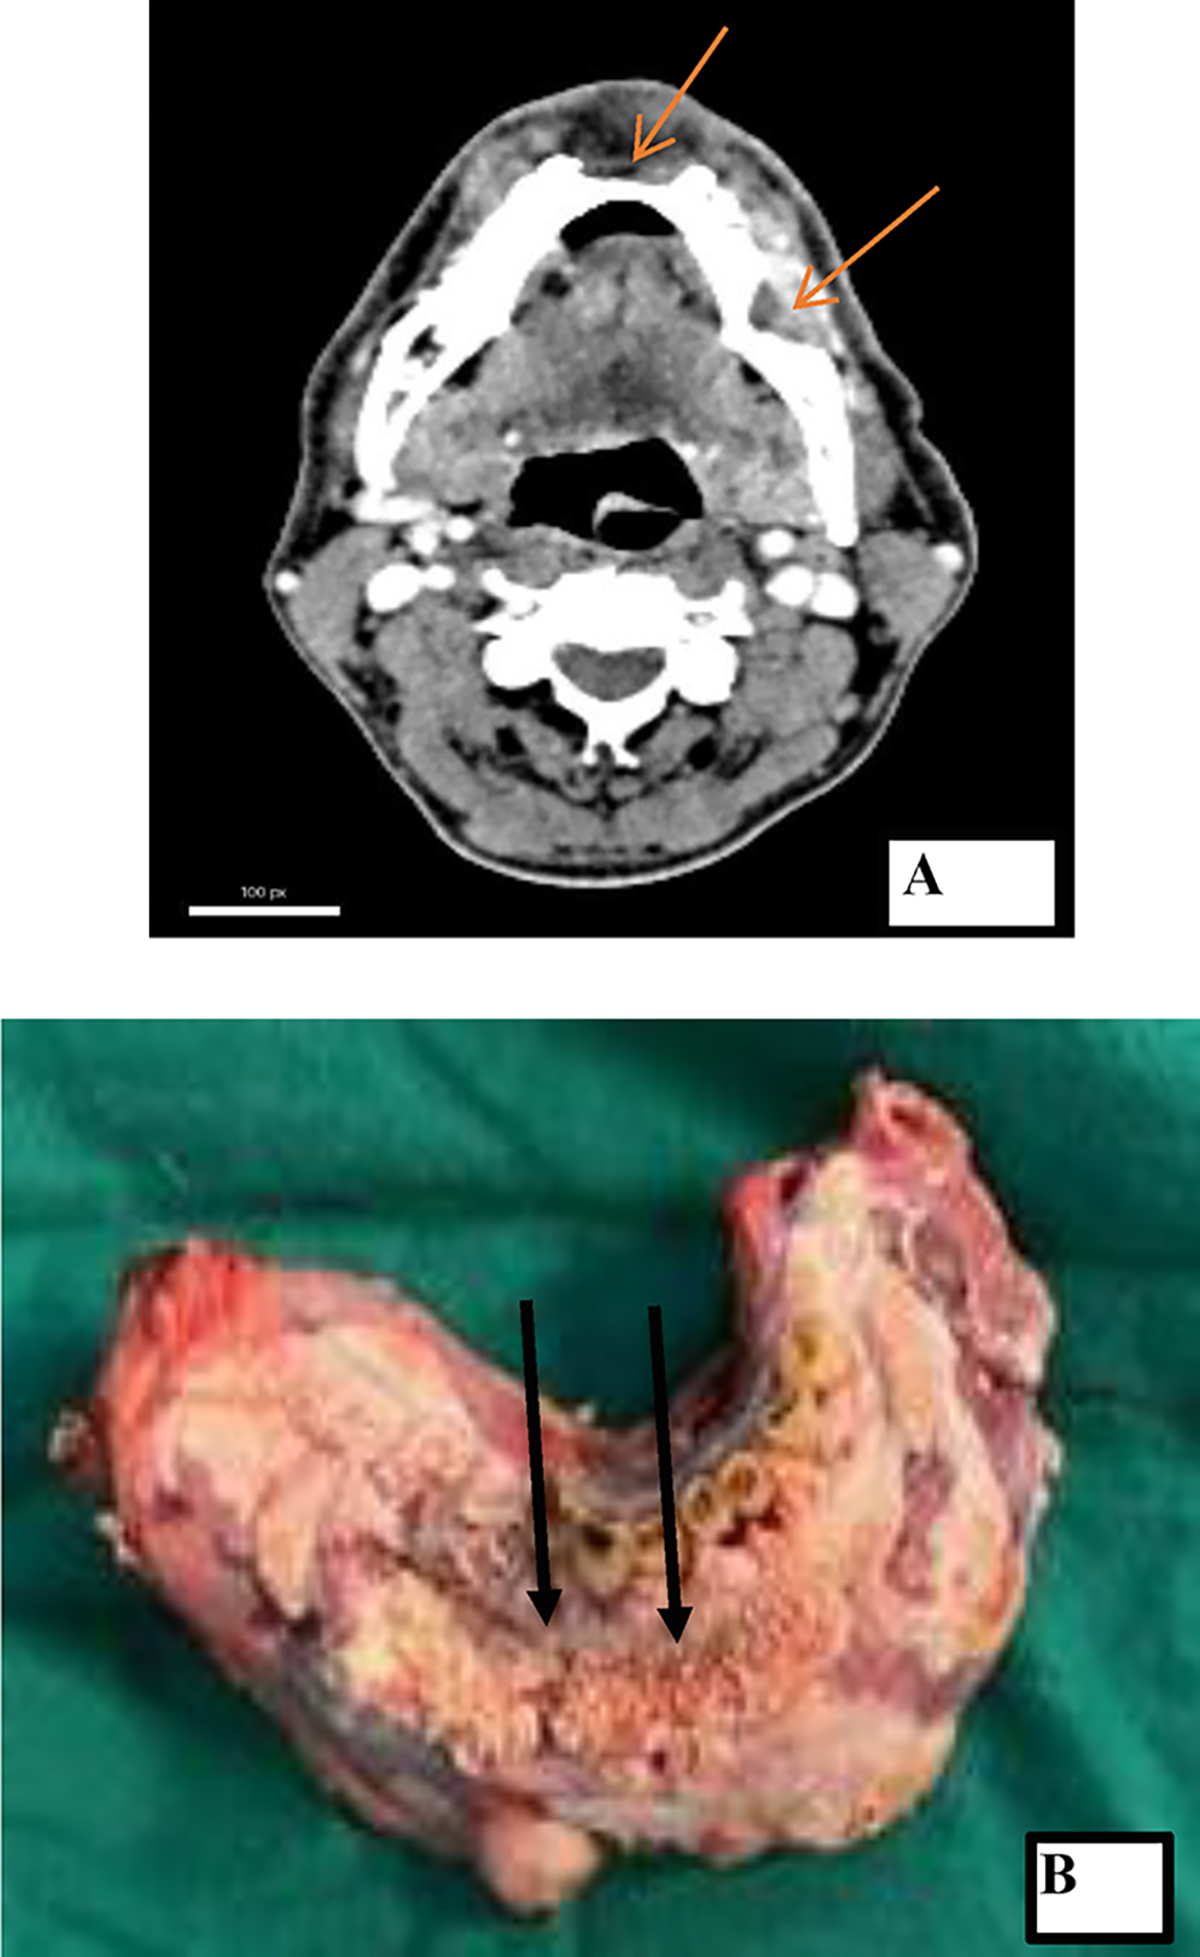

(A) Radiology showing bony erosion of the mandible (marked by red arrows) and (B) gross image of the tumour of the same patient showing the ulceroproliferative tumour involving lower gingivobuccal sulcus (black arrows) and mandible.